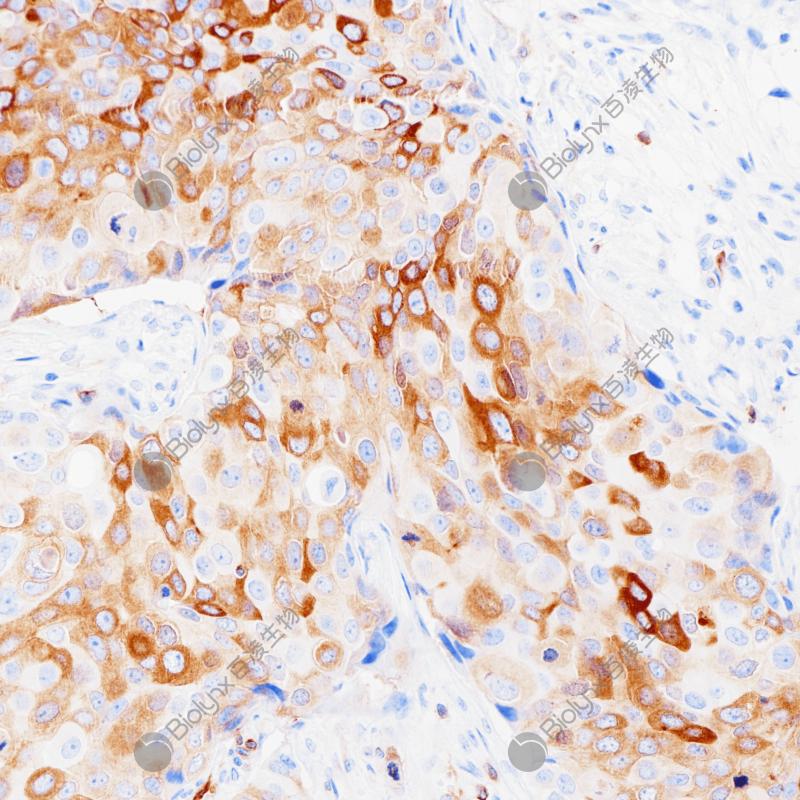

Arginase-1也称作肝型精氨酸酶,它作为尿循环的一个关键酶,在正常肝组织的肝细胞中的表达具有很高的特异性,胆管上皮细胞、肝窦内皮细胞、枯否细胞及血管内皮细胞均不表达。在肝细胞癌诊断中,分化良好及中度分化的肝细胞癌其表达率高达100%和92%,低分化肝细胞癌相对较低,其敏感性高于HepPar1和Glypican3.

细胞质/细胞核